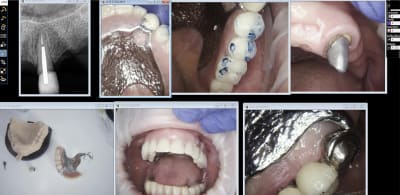

IC ceram 23 + stellite.

Plus longtemps que les dents restantes de l'autre coté. La patiente ne voulait pas passer au complet. Elle est au courant. Et passage au complet meme topo. One shot je me servirais de cette 23 comme base de réaccrochage de la camera. Ca s'appelle de l'efficience au sein d'un système de santé collectiviste. -)))

Idem que Chicot: Oneshot mais avec un peu plus d’éléments : 3IC, 8 CCM, 1 Stelitte. Aucune retouche autre qu’occlusale. Même Labo, c’est basique mais efficace

Pas mal. Attachements + augmentation de DV en plus.